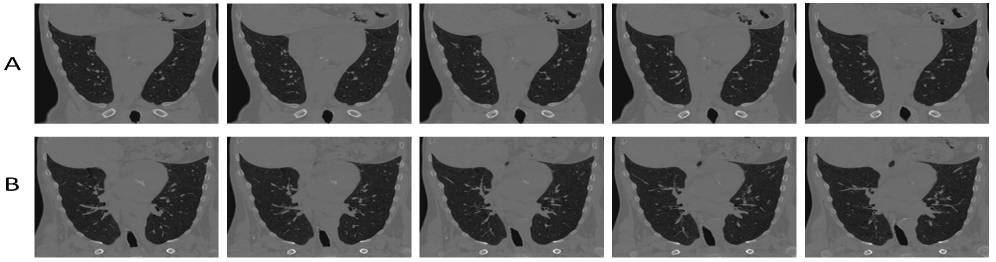

Refer to caption

Figure 2: Panel A shows coronal slices (71–75) from the fixed volume of Case 1 (DIRLab), while Panel B presents the corresponding slices from the moving volume.